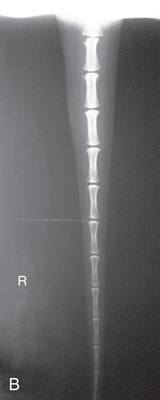

MEASURE: Thickest part of the tail.

CENTRAL RAY: Area of interest.

BORDERS: Four or five vertebrae on either side of the area of interest, or the full tail.